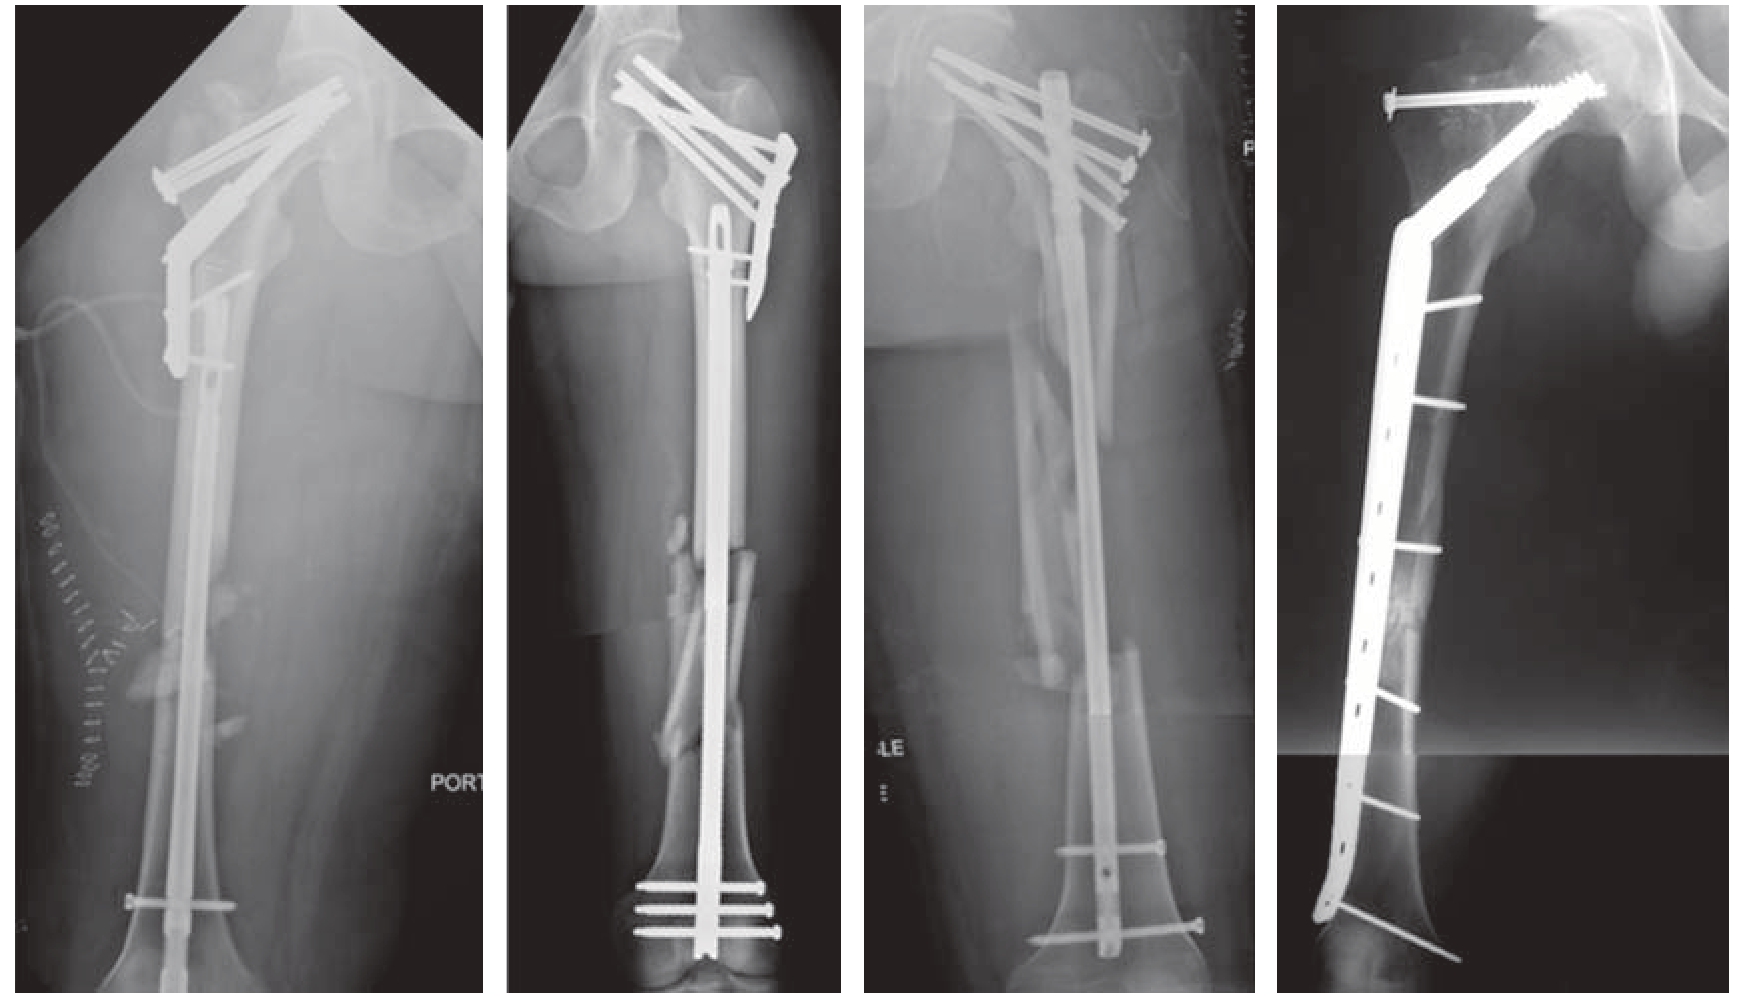

2018年,Jones和Walker在JAAOS上发表综述,总结了股骨干合并股骨颈骨折的治疗原则[10]。目前对于此类损伤,总的手术方法分为一体化固定和分体式固定,一体化固定的方法包括:头髓钉、长滑动髋螺钉和长锁定钢板;分体式固定的方法包括:逆行髓内钉加DHS/股骨近端锁定钢板/空心钉、顺行髓内钉加空心钉、加压钢板加DHS/股骨近端锁定钢板/空心钉。图10—3是目前常用的一些固定方法。相较于股骨干骨折,股骨颈骨折尤其是移位的股骨颈骨折的治疗更为重要,因为股骨颈骨折治疗的失败,特别是对于年轻患者,意味着可能接受关节置换等严重的后果。因此,目前的文献证据显示,相对于一体化固定,分体式固定可以降低股骨颈骨折复位不良的发生率,其中内翻复位是股骨颈骨折不愈合的主要原因。对于分体式固定来说,目前文献证据没有发现不同的内固定组合方式之间存在疗效差异,因此建议手术医生要完善术前计划,对于股骨颈骨折要尽量解剖复位,对于干部骨折则要恢复股骨长度、力线和旋转。

图10—3 目前常见的股骨干合并股骨颈骨折的固定方法